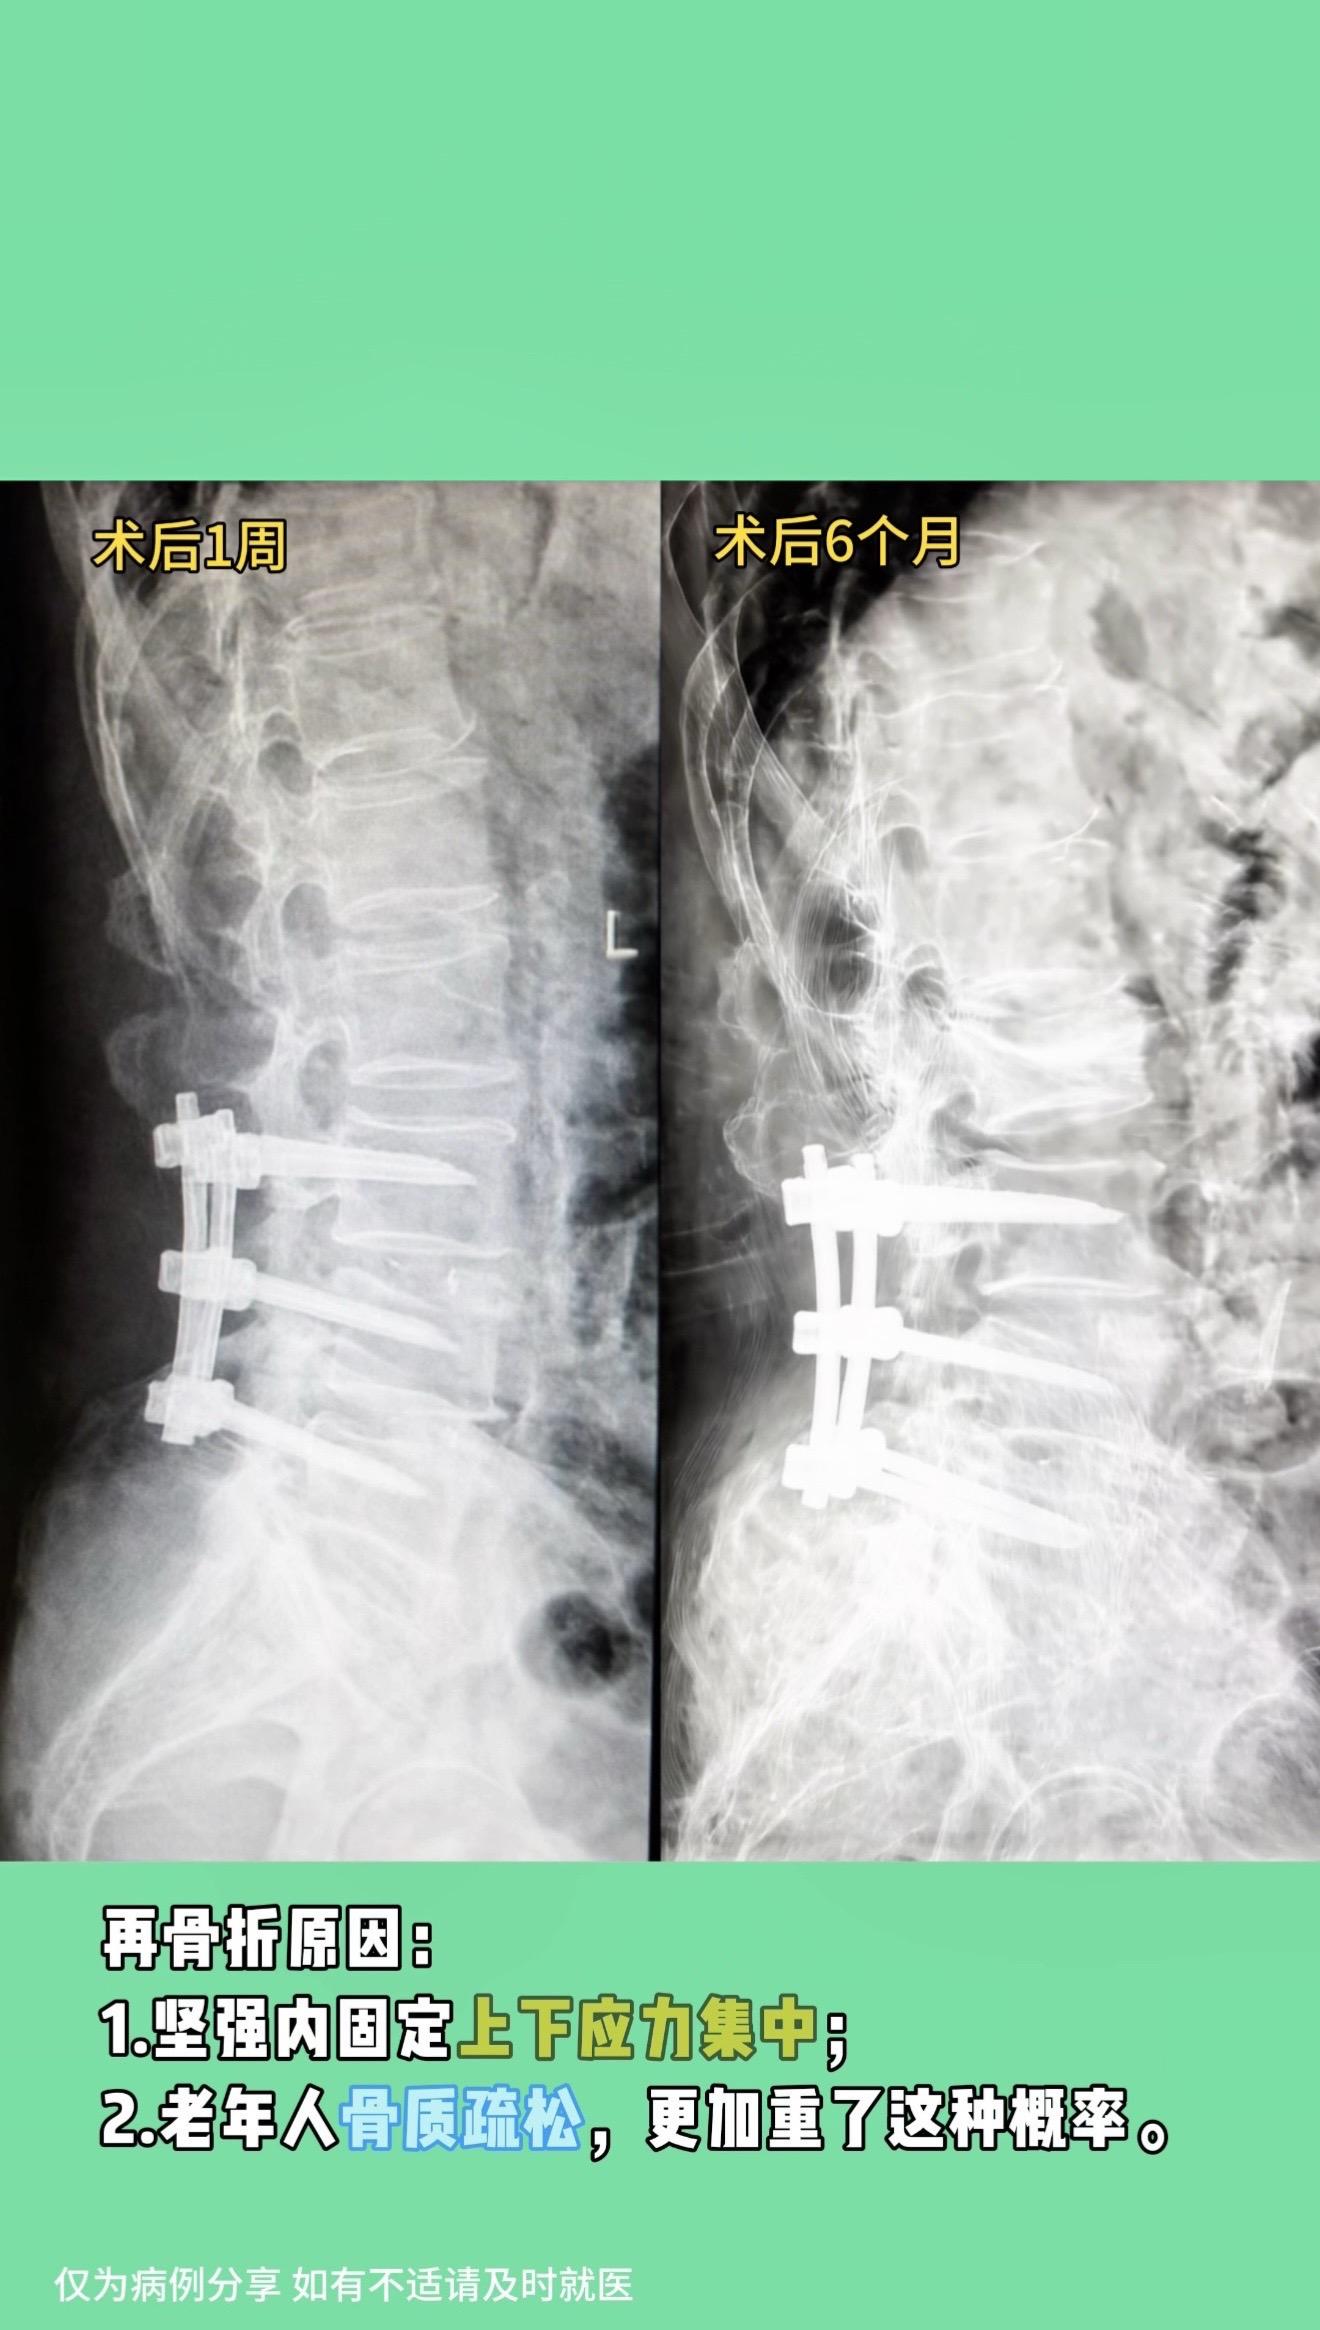

老年腰椎管狭窄症。老年腰椎管狭窄患者越来越多,很多伴有腰椎不稳定需要内固定,但坚强的内固定也带来很多问题,这是摆在患者和医生面前共同的难题。我们该如何选择? 真实病例分享: 70多岁男性,因严重腰椎管狭窄症半年前行腰椎内固定手术。术后恢复好,3月前去卫生间时扭了一下腰后,左下腹疼痛,现缓解。复查片子发现腰2压缩骨折,推测左下腹疼痛可能和腰2骨折神经刺激有关。 再骨折原因:1.坚强内固定上下应力集中;2.老年人骨质疏松,更加重了这种概率。